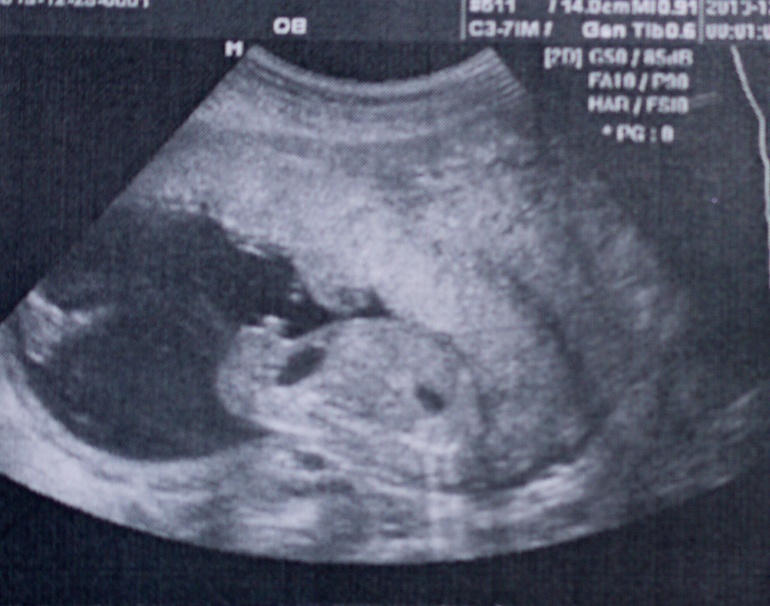

Вещи накупили белые и желто-салатово-ментоловые в основном, но встречаются и голубые;-) Это неспроста:))) 23 декабря я в тайне от всех посетила узи, тк терпелки не хватило дождаться середины января:) Много обсуждали мое прошлое узи тут.

Сказали, что сын!) Опытные мамы, подскажите, тут точно мальчик на картинке?:))) справа туловище и голова, слева нога, в середине вроде торчит писюн:)